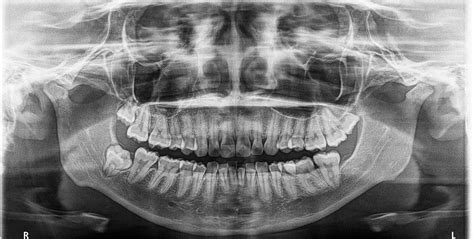

El diagnóstico preciso de la microdoncia es esencial para planificar un tratamiento adecuado. La utilización de radiografías dentales es una herramienta indispensable en el proceso de diagnóstico de la microdoncia. Las radiografías permiten a los ortodoncistas y dentistas evaluar el tamaño relativo de los dientes, identificar problemas de desarrollo y planificar las intervenciones específicas para corregir el problema y evitar complicaciones futuras.